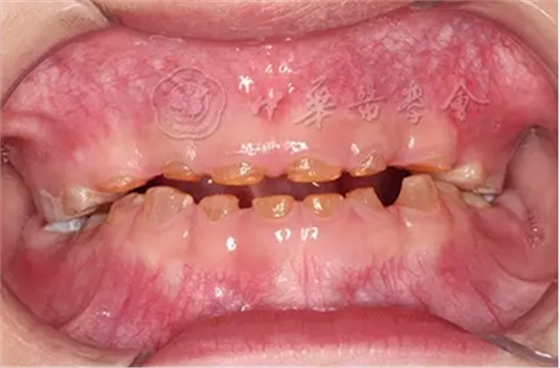

(1)疾病定義及口腔表現(xiàn):成骨不全是一種少見的先天性骨骼發(fā)育障礙性疾病,是由于Ⅰ型膠原ɑ1鏈編碼基因COL1A1和ɑ2鏈編碼基因COL1A2突變導(dǎo)致的結(jié)締組織遺傳性疾病,遺傳方式為常染色體顯性或隱性遺傳。成骨不全的臨床主要特征為多發(fā)性骨折、關(guān)節(jié)松弛、藍(lán)鞏膜、牙本質(zhì)發(fā)育不全和進(jìn)行性耳聾。根據(jù)疾病的臨床表現(xiàn)和遺傳方式分為4型,其中Ⅰ型和Ⅳ型有牙齒的表現(xiàn)?;純喝檠篮秃阊莱淑晟蛩{(lán)灰色半透明狀,釉質(zhì)正?;虬l(fā)育不全、易剝脫,牙齒磨耗明顯(圖4)。患者全口牙齒磨損嚴(yán)重,面下1/3垂直距離降低。影像學(xué)檢查顯示牙齒冠根交界處變窄,早期牙髓腔寬大,隨著牙齒的不斷磨耗,大量繼發(fā)性牙本質(zhì)沉積,髓腔明顯縮小甚至閉鎖,根管呈細(xì)線狀,嚴(yán)重時(shí)完全消失。組織病理學(xué)檢查可見釉質(zhì)牙本質(zhì)界變平,缺少正常貝殼狀結(jié)構(gòu)。牙本質(zhì)結(jié)構(gòu)異常,牙本質(zhì)小管數(shù)目減少、排列紊亂。

圖4 5歲成骨不全癥患兒乳牙呈琥鉑色,重度磨耗